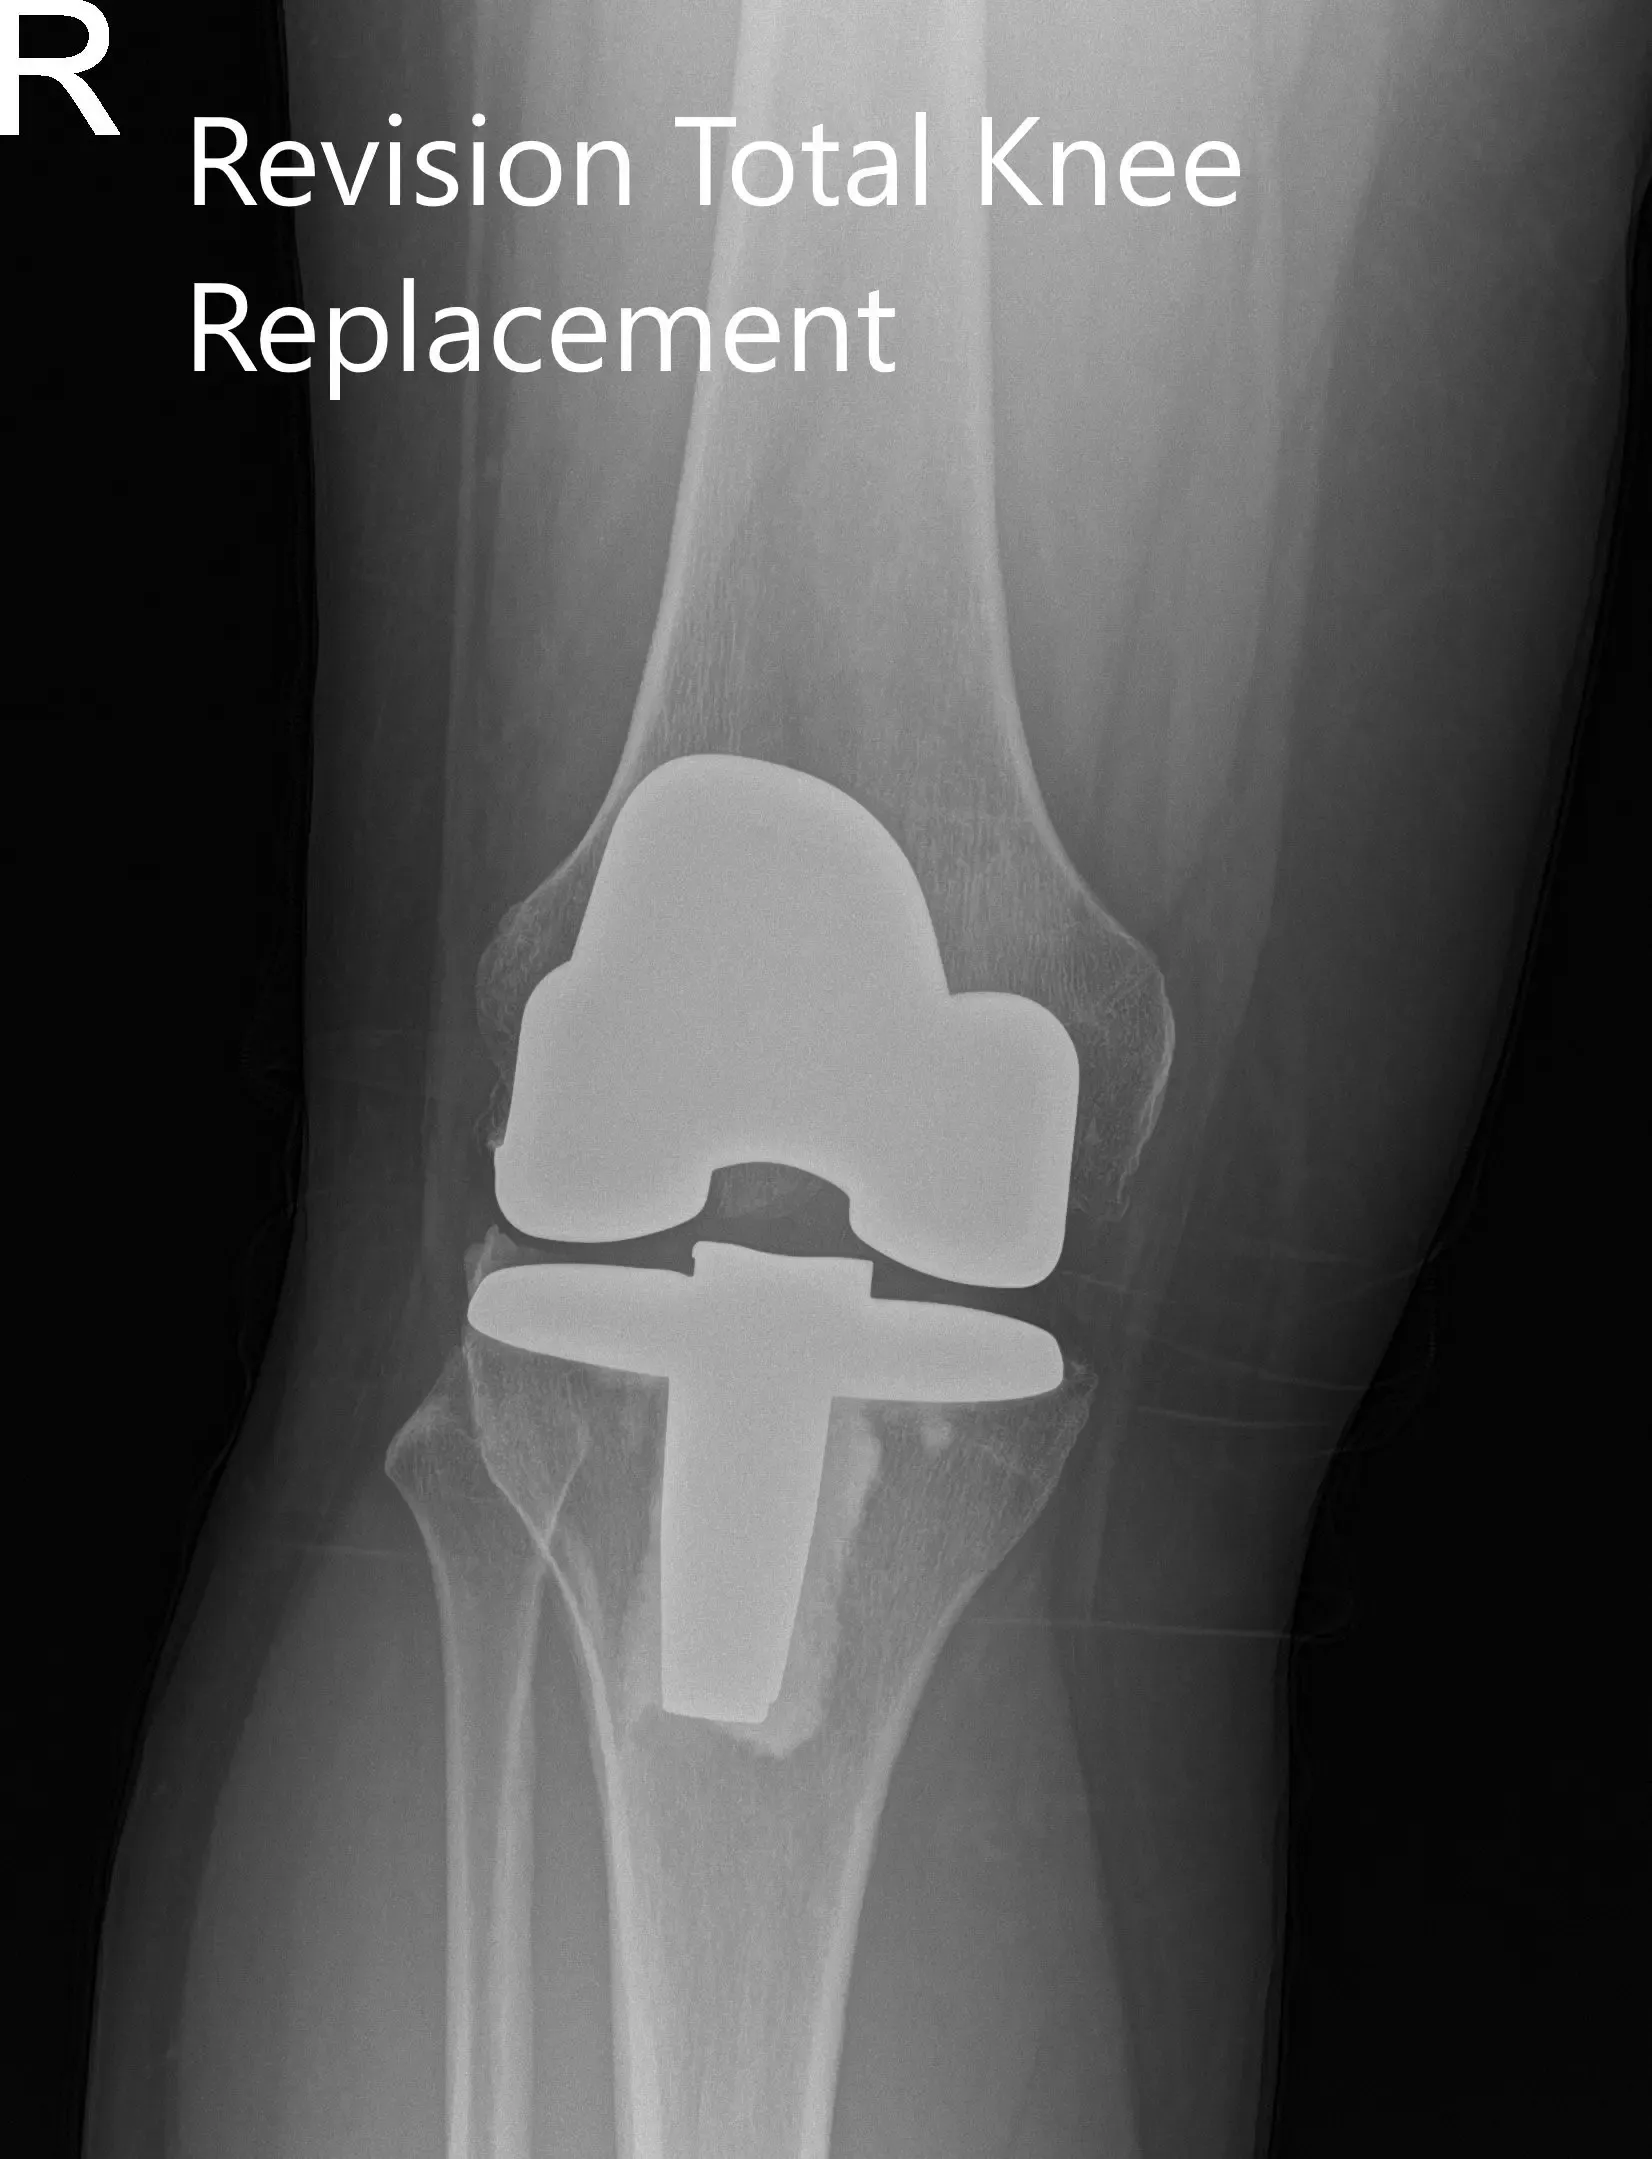

Postoperative x-ray showing the anteroposterior and lateral views of the right knee.

Post op his recovery was excellent. The pain was managed well with medications and he was ambulatory the same day of the surgery. He was given aspirin for deep vein thrombosis prophylaxis. He was advised physical therapy and home exercise program.

The sutures were removed uneventfully. The patient demonstrated a full range of motion with no pain at three months. The patient was able to walk without support and do her daily activities with ease. She was extremely happy with the outcome of the procedure.